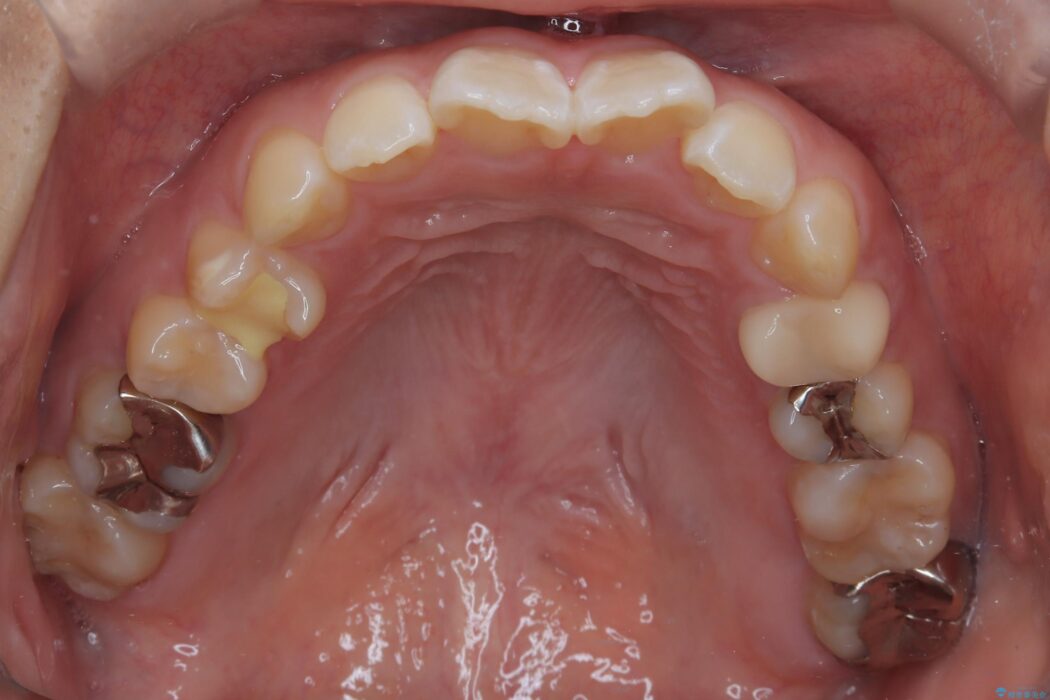

精密検査の結果、前歯を大きく後退させるスペースが必要と診断しました。

「前歯を下げたい」という患者様の強いご希望に応えるため、上下左右の第一小臼歯を抜歯。そのスペースを利用し前歯を奥へ移動させる治療計画を立案しました。

今回の矯正治療では、前歯を大きく後退させるスペースを確保するため、計画通り上下左右の第一小臼歯を抜歯しました。